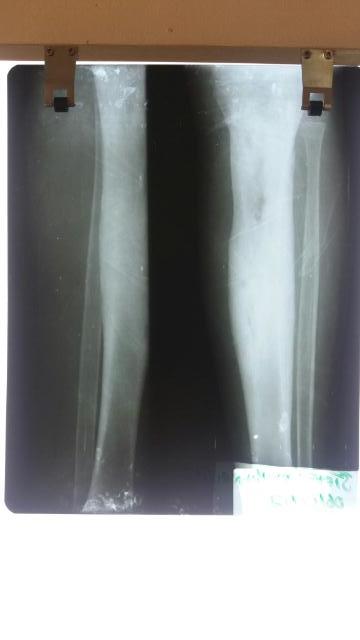

X-ray of both lower legs

The next day the radiology Virtual Doctor confirmed that the x-ray showed long-standing osteomyelitis of the right tibia (the larger bone in the lower leg). This is the area on the x-ray which looks very white and wider than the same bone on the other leg. Above this is a blacker or lucent area which might be an abscess. The radiologist also remarked that it can be difficult to tell the difference between a serious and longstanding infection and a malignant process (cancer).

The paediatric surgeon agreed that this looked like a long standing (chronic) osteomyelitis and would need surgery to remove dead tissue and a long, more than 6 week, period of intravenous antibiotics. Ideally he needed more imaging to be sure about the underlying problem. He needed an orthopaedic surgeon in Zambia which of course would mean travelling, possibly to the capital to a hospital with the right facilities.